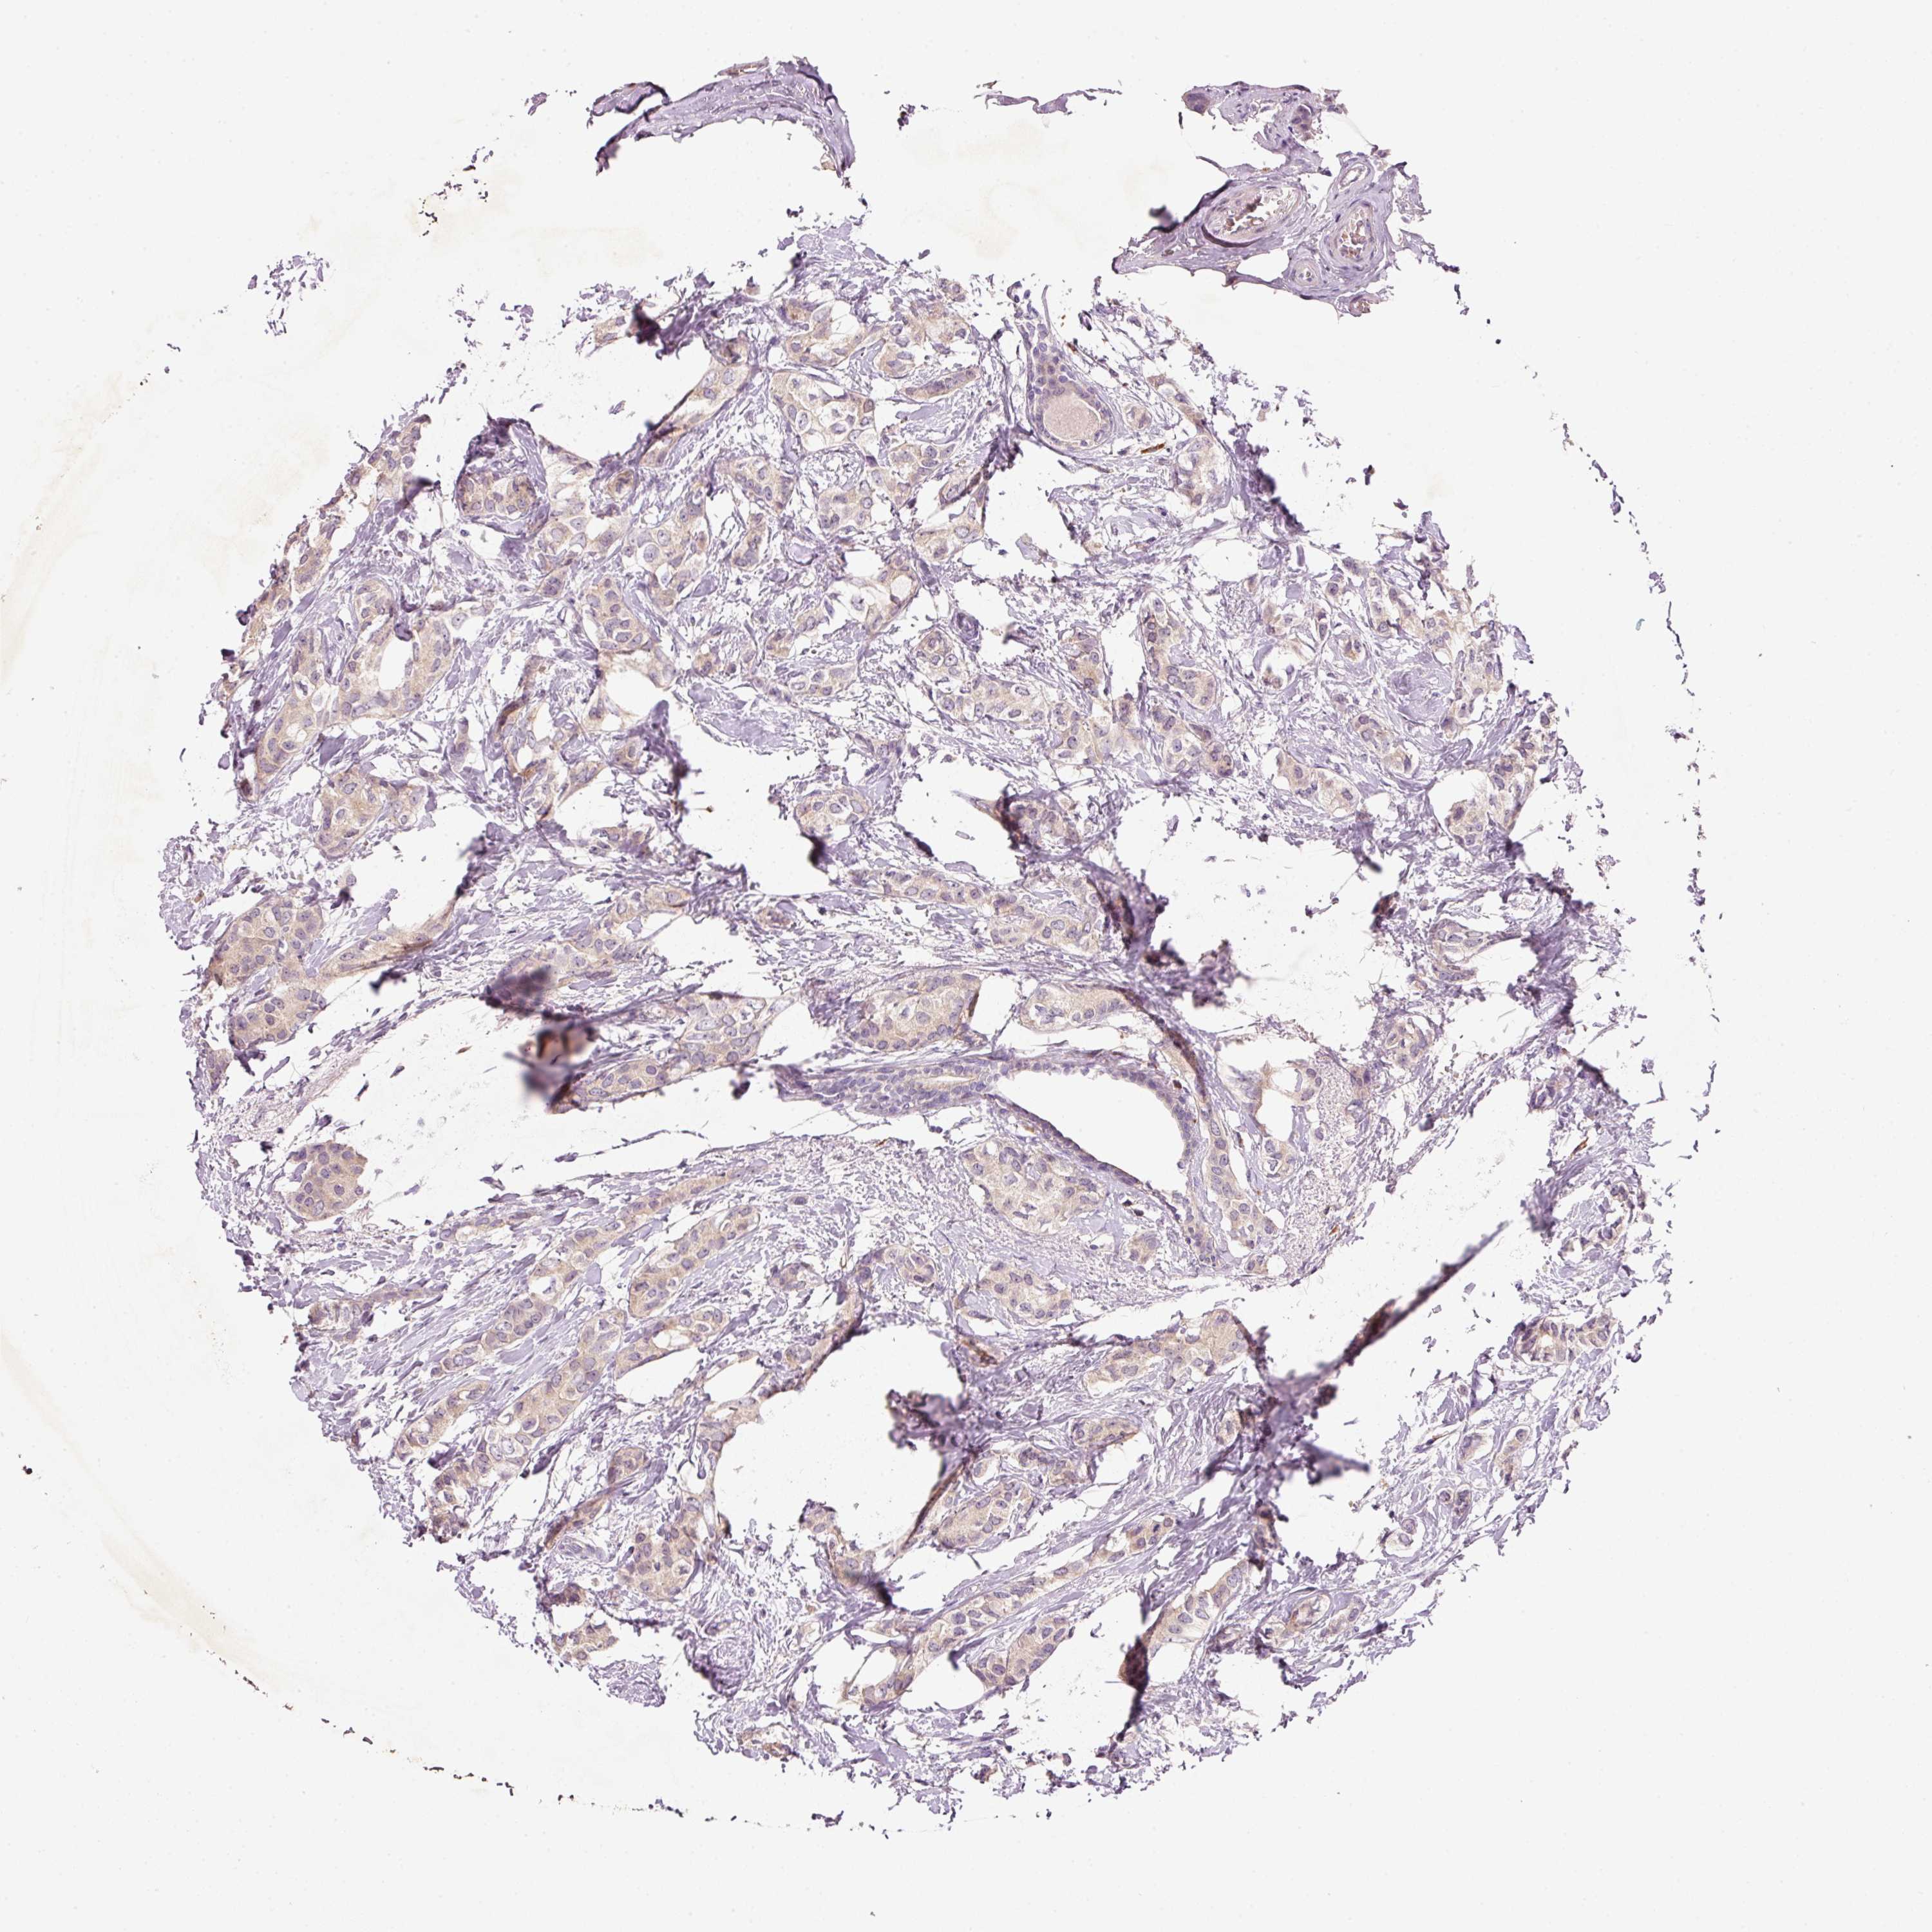

CANCER BREAST CANCER Show tissue menu

BRCA TCGA BRCA VALIDATION PROTEIN EXPRESSION

ANTIBODIES

AND

VALIDATION